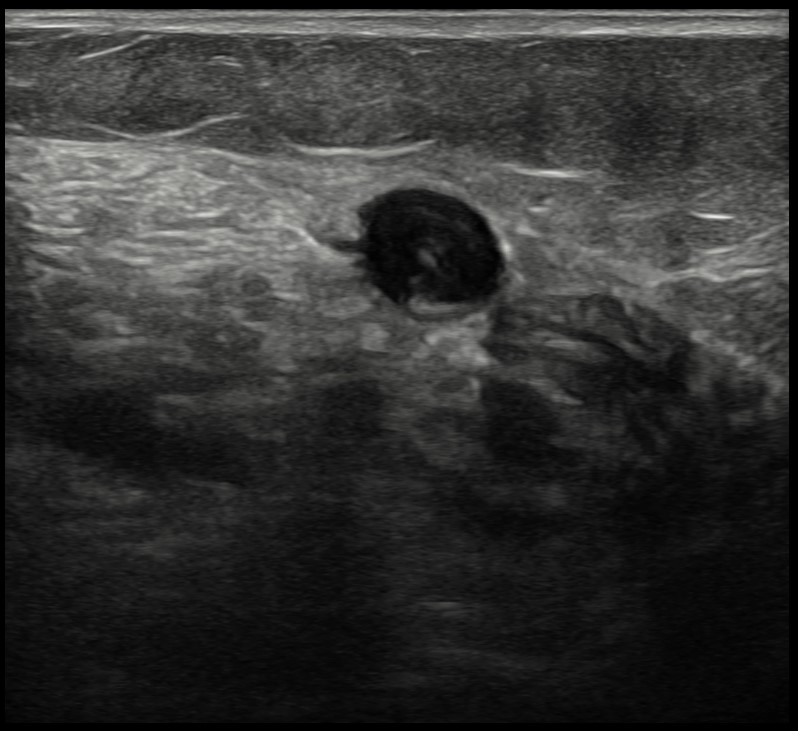

Mujer de 71 años que acude al Centro de Salud por dolor en la región superior de la pantorrilla izquierda. Refiere cuadro de lumbalgia en tratamiento analgésico con mejoría progresiva hasta seis días antes, cuando el dolor comenzó a irradiarse al miembro inferior izquierdo, focalizándose en la pantorrilla. Describe dificultad para la deambulación, sin alivio en reposo, y percepción de hinchazón y frialdad de la extremidad. Niega disnea, dolor torácico u otros síntomas sistémicos.Hallazgos ecográficos

Sistema venoso profundo no compresible en toda la pantorrilla izquierda, con material ecogénico intraluminal y ausencia de flujo en Doppler, hallazgos compatibles con TVP distal. Edema subcutáneo en región gemelar presente.Pruebas complementarias